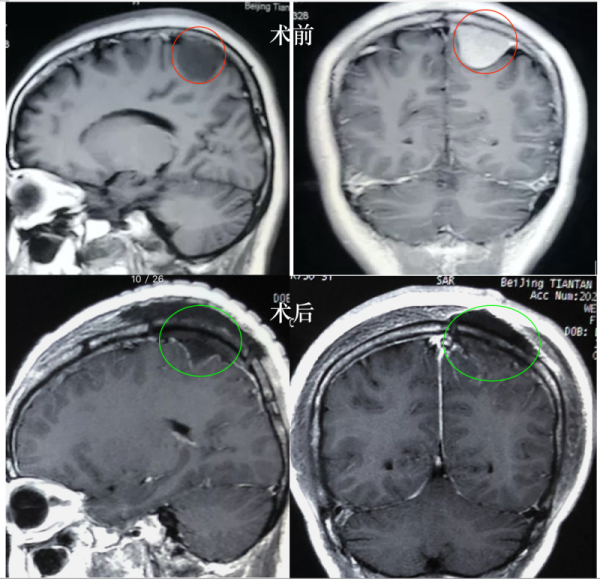

35岁女士,2020年2月在A医院确诊为左顶凸面占位脑膜瘤,大小约3cm,6月实行全切切除。病理分析为who1-2级,Ki67为15%,建议咨询放疗专家。

总结:WHO病理结果本身也受病理医师、检测方法的影响,甚至术者所取标本组织的差异也会决定病理结果的不一致,临床中这样的情形偶尔可见。在该病例中,凸面脑膜瘤靠近运动功能区,手术全切,WHO分级及Ki67指数不同医院结果不一样,患者病理提示I级或I-II级,Ki67指数5%-15%,放疗或不放疗都有潜在“收益和风险”。根据在德的经验和治疗指南,结合病人年龄、靠近功能区、影像特点、手术全切、病理结果及术后无明显功能障碍,建议密切观察MR及随访,可暂不放疗,如果肿瘤复发,病情允许,建议再次手术治疗。病人遇到这样的情况时,多咨询是对的,建议能较终明确病理结果,若情况允许可以再取标本组织重做病理切片。同时也是建议选择较了解患者病情的好的主管医师就诊,根据病人情况综合决定治疗方案,不同神经外科医师、放疗科决策者的经验和认识不同、病患的需求不同,都会造成治疗建议的差异,况且很多治疗方案都是有潜在的益处和风险,病人个体也具有很大差异,对于很多尚有争议的领域,医学上也没有“统一、正确”的方案,很多时候医者也只能给出医学角度的建议。